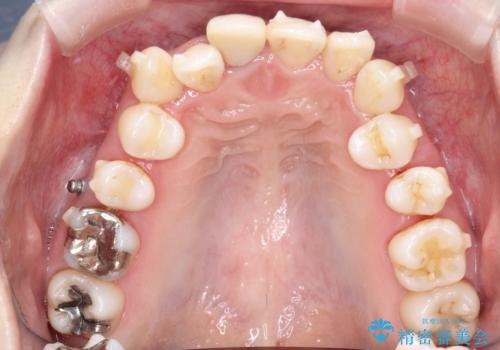

上下のガタガタのマウスピースによる非抜歯矯正

- 上下のがたつきを主訴に来院された患者様です。

上下の前歯と奥歯にがたつきがありました。

上下の奥歯を後方に移動させるのと、歯と歯の間をわずかに削ることでスペースを作り、歯を並べる計画としました。